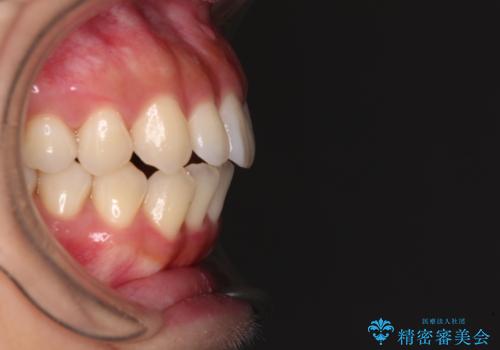

- 上下前歯の隙間と口元の出っ張った感じを気にして来院された患者様です。

上下の隙間は舌突出癖によるもので、またその癖により前歯が前方に出ている状態でした。

口元の出っ張りを改善するため、上下左右第一小臼歯4本を抜去し、ワイヤー装置にて矯正治療を行うこととしました。